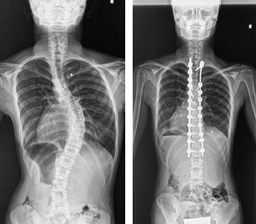

後方矯正固定術

せなかを切開してチタンなどで作られた椎弓根スクリューをせぼねに挿入して、ロッドと呼ばれる金属のバーで固定して、せぼねの矯正と固定を行います。術後に手術部の安静を保つために装具を3-6ヶ月程度着用します。